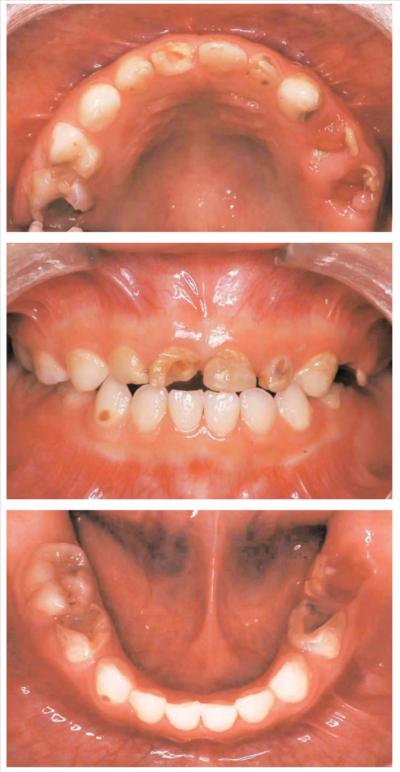

3歳児の口腔内写真を別に示す。

3歳児歯科健康診査の齲蝕罹患型で該当するのはどれか。1つ選べ。

a. O 型

b. A 型

c. B 型

d. C1 型

e. C2 型